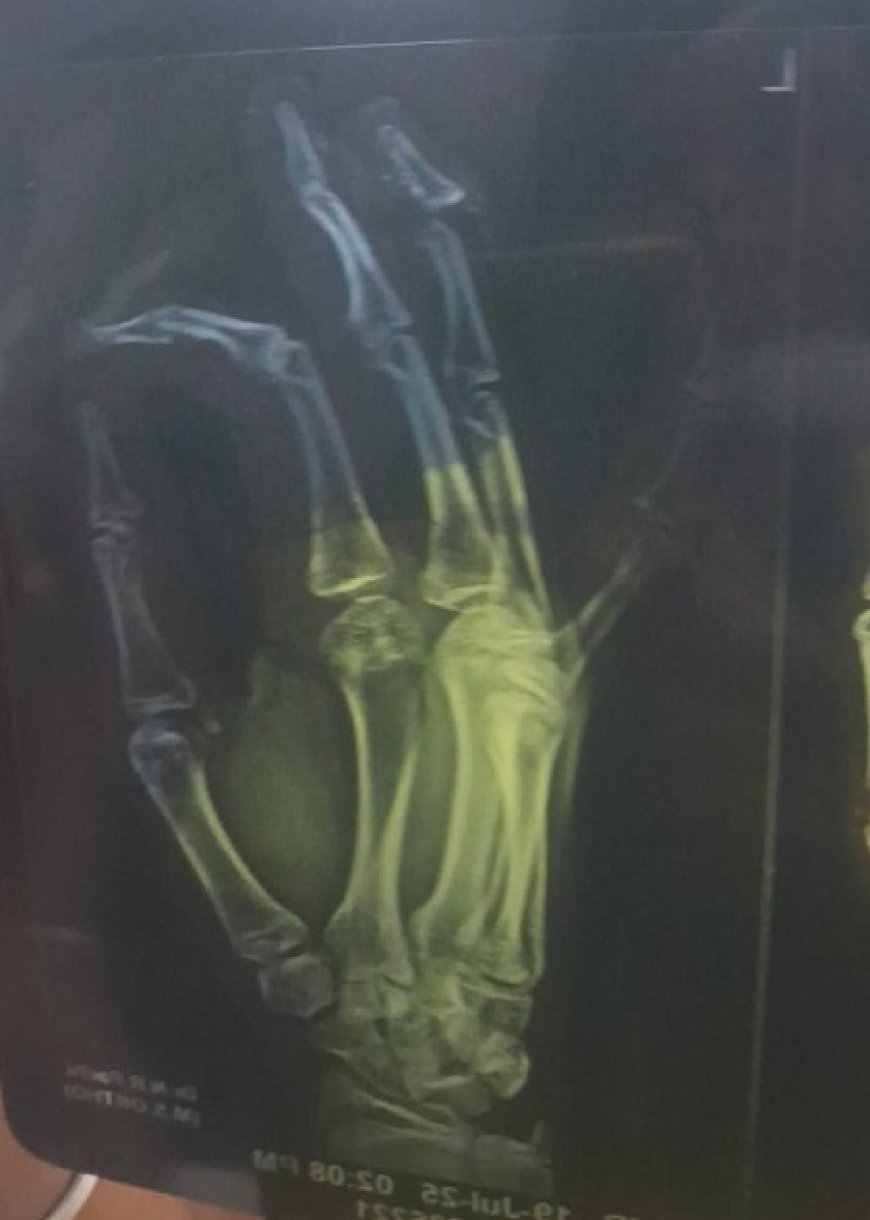

जहाँ एक फ्लाई ऐश ब्रिक्स की फैक्ट्री में एक युवक की उंगली जरा सी कट गई थी फैक्टरी के संचालक और परिजनों द्वारा उसे गौठाना क्षेत्र स्थित फ्रेक्चर हॉस्पिटल लेकर पहुँचे जहाँ परिजनों द्वारा आरोप लगाया गया है कि उसकी उंगली का इलाज करने की जगह डॉ ने अपने बिल को बढ़ाने के लिए गलत इलाज करते हुए उसे कोई गलत इंजेक्शन लगा दिया जिससे युवक की हालत बिगड़ने लगी मरीज की हालत बिगड़ते देख अस्पताल प्रबंधन ने परिजनों से युवक को रेफर किये जाने की बात की जिसके बाद युवक को परिजन नागपुर ले जाने लगे पर रास्ते मे ही युवक ने दम तोड़ दिया।